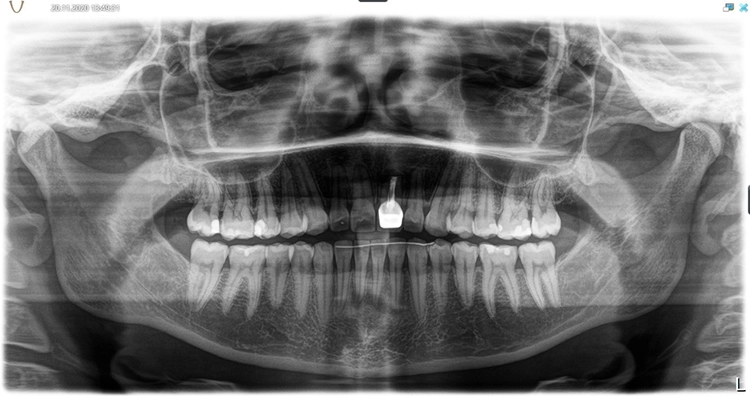

In Vorbereitung auf die Implantatplanung und das CAD/CAM-Herstellen der temporären Krone erfolgte eine digitale Datenerfassung mit dem Intraoralscanner (Trios 3, 3Shape). Der Datensatz der Ausgangssituation sollte später bei der CAD-Konstruktion hilfreiche Informationen liefern (Abb. 3). Mit dem Scan ist die Ausgangssituation digital archiviert und steht jederzeit zum Abruf bereit. Zudem wurde ein DVT für die Planung der Implantatposition am dreidimensionalen Bild vorgenommen und der DICOM-Datensatz in die Implantatplanungssoftware importiert (Abb. 4 und 5).

Theoretisch kann in der Planungssoftware der STL-Datensatz aus dem Intraoralscanner (Ausgangssituation oder Set-up) hinzugezogen und so die Implantatposition aus prothetischer Sicht ideal definiert werden. Im vorgestellten Fall ergab die 3D-Diagnostik ein ausreichend stabiles Knochenvolumen in regio 21. Geplant worden ist die Insertion eines BLX-Implantates (Straumann).